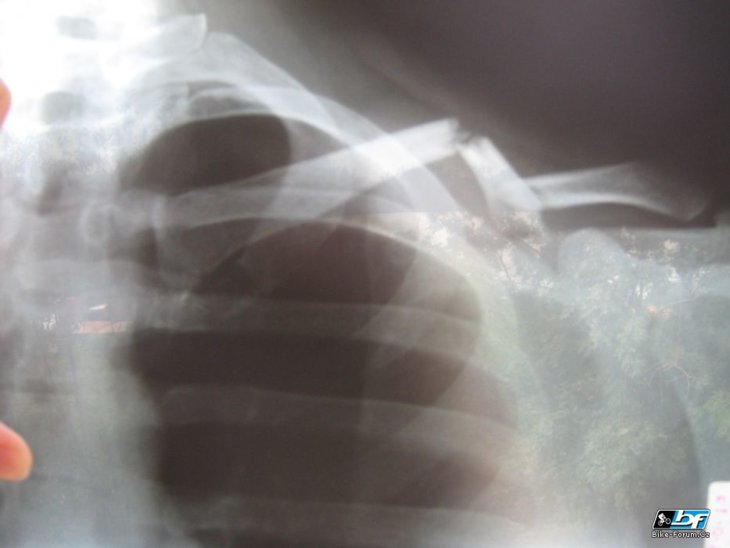

Dvojitá zlomenina levé kliční kosti. Snímek dva týdny po úraze.

já ti nevím jestli si z nás neděláš prdel. koukal jsem na svůj snímek a kost co jám mám rovně máš ty do písmene Z. To mi nepřijde jako moc ok a nechápu jak by to mohlo srůst bez komplikací. Ale nejsem doktor…